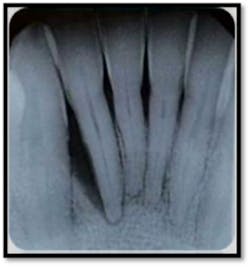

#26: 12mm MF and ML (above left); BOP, Class ll mobility (above right)

Note the severe vertical bone loss on the mesial of #'s 8-9